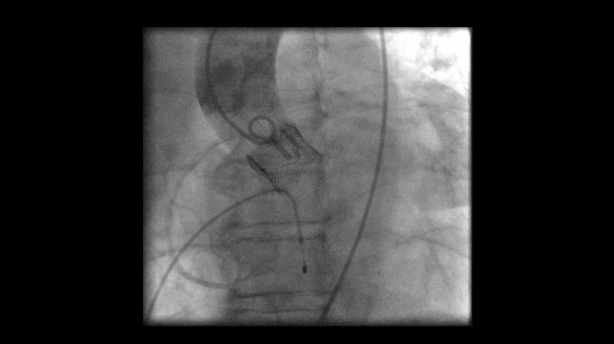

在一些合適的病友,甚至能在局部麻醉之下,即可接受主動脈瓣膜的置放。本項技術皆於本院新建之整合型手術室(hybrid operation room)進行,且與歐美同步使用最新之Philips Epiq 3D重組影像來輔助心導管瓣膜手術的置放。這項手術需要心臟內、外科的團隊通力合作,術前仔細的評估與術後密切的追蹤。

使用最新一代Evolut Pro瓣膜置放之後,病友會有較佳的預後